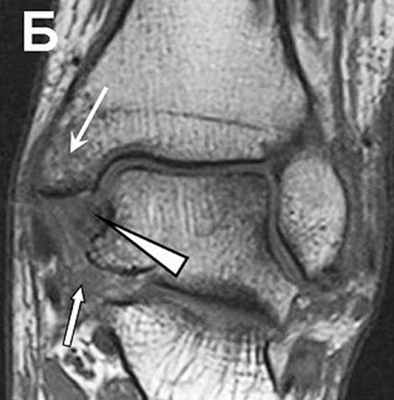

(Справа) У этого же пациента при рентгенографии голеностопного сустава в боковой проекции визуализируется отрывной перелом области прикрепления ЗНМС. Кроме того, спереди в суставе выявляется выпот. (Слева) Пациент, у которого при наружной ротации возникла нестабильность голеностопного сустава. При МРТ в коронарной плоскости на Т2 ВИ в режиме FS на срезе, проходящем через задний край голеностопного сустава, определяются частичный разрыв ЗНМС и нарушение целостности межлодыжковой связки.

(Справа) У этого же пациента при МРТ в коронарной плоскости на Т2ВИ в режиме FS на срезе, проходящем ближе кпереди, визуализируется пучок ПНМС, который сместился в область синдесмоза. Распространение жидкости краниально на расстояние >1 смог нижней суставной поверхности большеберцовой кости указывает на разрыв связки, входящей в состав синдесмоза. Выявляются повреждение дельтовидной связки и отек костного мозга медиальной лодыжки. (Слева) При МР-артрографии в коронарной плоскости на Т1ВИ в режиме FS определяются разрывы 3FIMC, межкостной и межлодыжковой связок. При МР-артрографии с контрастным усилением разрыв увидеть проще, чем при нативном исследовании.

2. МРТ при повреждении межберцового синдесмоза:

• В норме связки видны как в коронарной, так и в аксиальной плоскостях

• ПНМС обычно состоит из двух пучков:

о В аксиальной плоскости два пучка связки могут быть ошибочно расценены как части одного разорванного пучка

• ЗНМС лучше всего видна в аксиальной плоскости:

о Отрывной перелом области прикрепления к большеберцовой кости или разрыв среднего отдела связки

о Отрывной перелом встречается чаще, чем разрыв связки

• Межкостная связка лучше видна в коронарной плоскости:

о Распространение жидкости более чем на 1 см выше нижней суставной поверхности большеберцовой кости указывает на разрыв связки

• Позволяет обнаружить ротацию малоберцовой кости относительно большеберцовой кости